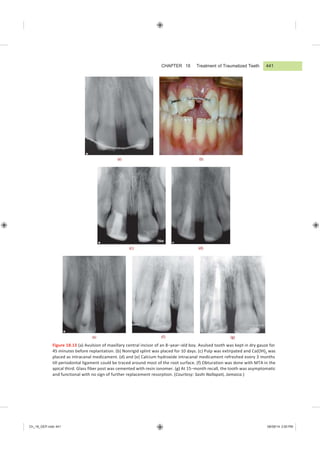

Figure 18.13 (a) Avulsion of maxillary central incisor of an 8āˆ’yearāˆ’old boy. Avulsed tooth was kept in dry gauze for

45 minutes before replantation. (b) Nonrigid splint was placed for 10 days. (c) Pulp was extirpated and Ca(OH)2 was

placed as intracanal medicament. (d) and (e) Calcium hydroxide intracanal medicament refreshed every 3 months

till periodontal ligament could be traced around most of the root surface. (f) Obturation was done with MTA in the

apical third. Glass fiber post was cemented with resin ionomer. (g) At 15āˆ’month recall, the tooth was asymptomatic

and functional with no sign of further replacement resorption. (Courtesy: Sashi Nallapati, Jamaica.)